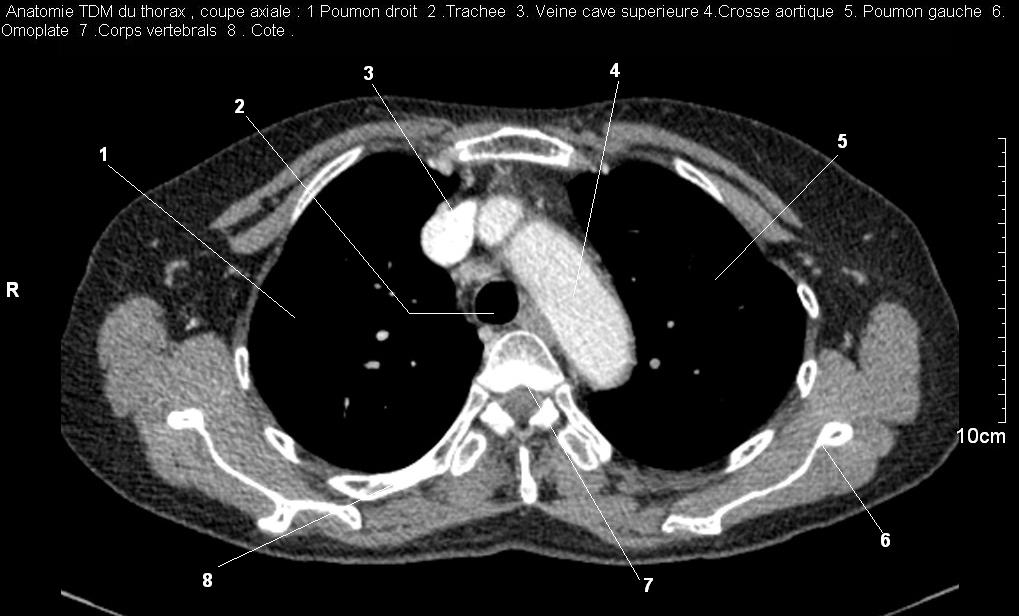

| Images

radiologiques normales du poumon ,la plevre , le diaphragme , et le mediastin

Radioanatomie pulmonaire ( image radiologie

thoracique normale )- La Tomodensitometrie du thorax (

coupes axiales fenetre mediastinale ) |

Les fenetres mediastinales permettre

d'etudier anatomie du mediastin et les structures vasculaires

en coupes axiales de 0,5-1cm sur le thorax . Et si elles

sont opacifiees par produit de contrast elles sera se donnent des resutats

suivantes : |